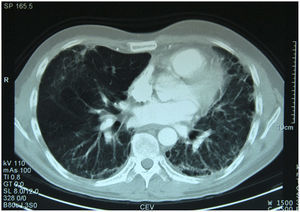

Tras 9 meses de tratamiento inmunosupresor (CFM en pulsos trimestrales, CyA a dosis de 5mg/kg/día y corticoides en pauta descendente), no recidivó el neumomediastino, el paciente permaneció estable y recuperó su capacidad para deambular. La gasometría arterial basal mostró PO2 de 60mmHg y PCO2 de 37mmHg, con saturación de oxígeno del 91%. Las pruebas de función respiratoria mostraron un patrón restrictivo con disminución de la difusión pulmonar de oxígeno. En la TC persistió una amplia panalización bilateral (fig. 2), con la desaparición de las lesiones en vidrio deslustrado. Dadas la gravedad de la alteración funcional respiratoria residual y la estabilidad de las imágenes radiológicas, se remitió al paciente a su hospital de referencia para valorar trasplante pulmonar.